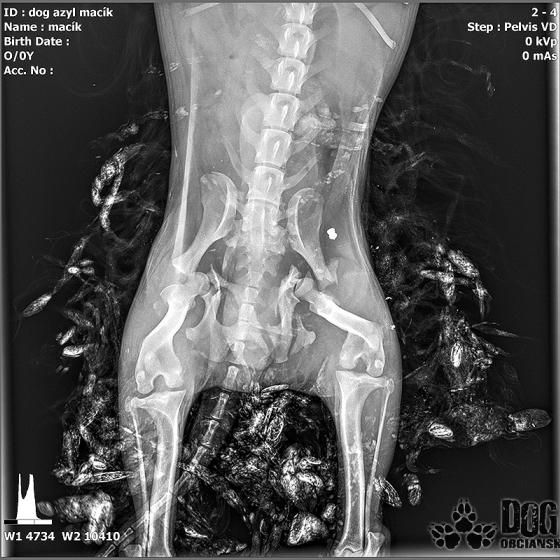

Vianoce nám klopú na dvere a mali by to byť sviatky radosti a pokoja. No u nás nebudú a pre malého Jamesa už vôbec nie. Malého Jamesa sme prijali s mnohonásobnými fraktúrami panvy. Presnejšie, s obojstrannou iliosakrálnou luxáciou/fraktúrou, viacnásobnou fraktúrou panvy, vrátane fraktúry kranialneho acetabula obojstranne. Áno, znie to hrozivo a keď si pozriete snímky z RTG, bude to ešte hrozivejšie (ďalšie snímky ešte doplníme).

Čakali ho teda štyri, veľmi náročné ortopedické operácie, takže sa musel trocha posilniť. Do starostlivosti si ho vzala MVDr. Panyi Terzieva a 17.11. mohol absolvovať prvú operáciu. V "prvom kole" krpec zvládal anestézu tak dobre, že sa rovno mohli spojiť dve operácie a tak sa celá ľavá strana dala do poriadku. Zostal samozrejme naďalej hospitalizovaný. Ďalší zákrok sa naplánoval na 20.11. a našťastie opäť všetko prebehlo hladko, a zoperovala sa celá pravá strana(nechceme sa dlho rozpisovať, prikladáme lekársku správu). James bol prepustený 24.11. ako chodiaci pacient a bez problémov ovládal aj vylučovanie! Je to priam zázrak, za ktorý opäť vďačíme MVDr. Vatolíkovi a jeho teamu.